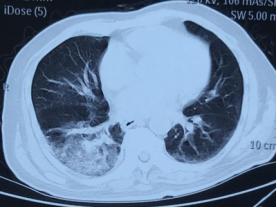

5、哪些免疫功能低下CAP患者中,最初的经验性治疗应覆盖 肺孢子菌肺炎?

-存在双肺弥漫性间质浸润或肺泡斑片影且尚未接受PCP预防治疗的患者

-CD4+T淋巴细胞计数<200个/μL(或百分比<14%)

-细胞免疫严重受损者(例如联合使用糖皮质激素与细胞毒药物)

-主要症状为发热、干咳和进行性呼吸困难

病原学:痰、BALF六胺银染色以及PCR分子诊断。辅助诊断:LDH升高、G试验升高。